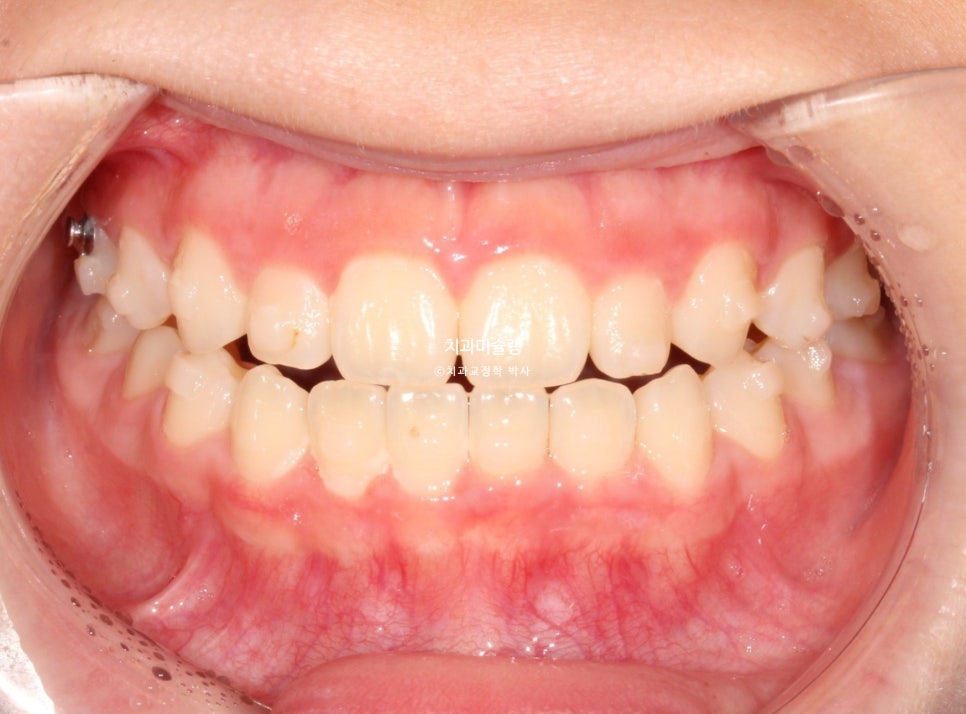

치료 완료 시 결과

중심선은 잘 맞으며 절단교합으로 인항 개방교합은 해소되었습니다.

어금니 교합관계는 1급을 달성.

3급 교합관계를 1급으로 만들기 위해 치료기간 내내 3급 고무줄을 사용했습니다.

결과가 성인교정치료 결과에 준한만큼 유지장치도 성인과 동일하게 들어갑니다.